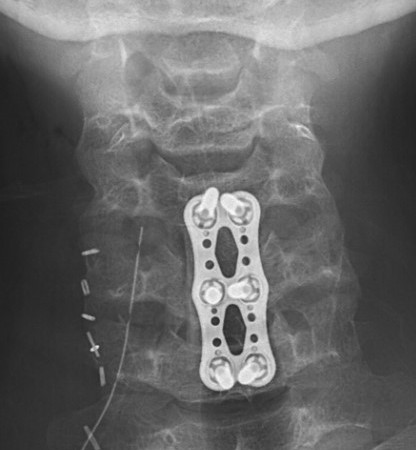

A. Anterior corpectomy & fusion with tricortical graft + plate

B. Anterior corpectomy & fusion with mesh cage + bone graft + plate

+/- Supplemental posterior fixation / cervical lateral mass screws

Anterior corpectomy and tricortical graft